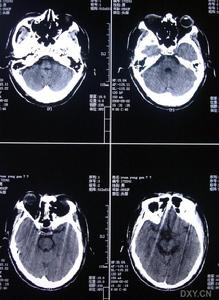

影像學檢查示:患者姐弟的CT均可見,但當地的CT顯示欠清楚。患者的頭顱CT可見多發白質變性;MRI清晰可見多發白質變性及小梗死病灶,病灶大小不一,均呈長T1、長T2信號,病灶累及雙側半球、腦室周圍、腦幹、橋腦,小腦未見病灶;梗死灶分布在底節區,MRA(血管的磁共振影像)顯示顱內血管正常。